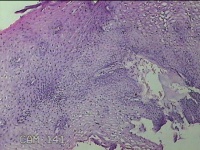

宫颈1点、6点、10点组织

性别

女

年龄

35岁

临床诊断

宫颈炎性疾病

一般病史

宫颈高危HPV52阳性一年余,81阳性,TCT未见内瘤病变及恶性细胞。

标本名称

大体所见

1.“宫颈1点组织”:灰白粉红色组织0.7x0.3x0.2cm一块。 2.“宫颈6点组织”:灰白粉红色组织0.7x0.3x0.2cm一块。 3.“宫颈10点组织”:灰白粉红色组织0.7x0.5x0.2cm一块。

图1